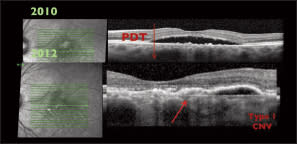

He cited more recent evidence that shows PCV is usually not in the choroid but rather is found above Bruch's membrane and is thus a variant of type 1 neovascularization. He said that OCT can help visualize this (Figure 1), demonstrating by showing cases of PCV with polyps above the choroid (Figure 2). Dr. Freund used histological slides to demonstrate that PCV seems to originate from type 1 neovascular membranes as vessels found at the margins of these membranes tend to mature and dilate (Figure 3).

Figure 1. In many cases of PCV, the polyps are not in the choroid but rather above Bruch's membrane.

In a third example, a patient presented CSC associated with choroidal hyperpermeability. The following year, a thickened choroid and dilated choroidal vessels were evident, and the patient was treated for CSC. Dr. Freund treated the patient with photodynamic therapy. He indicated that his practice has seen some patients develop type 1 neovascularization after repeated PDT treatments. Two years after PDT, the patient had new-onset type 1 neovascularization (Figure 10). This case indicates for Dr. Freund that cases of CSC treated with PDT should be carefully monitored for neovascularization.

Figure 10. Two years after PDT, this patient developed a new-onset type 1 neovascularization.